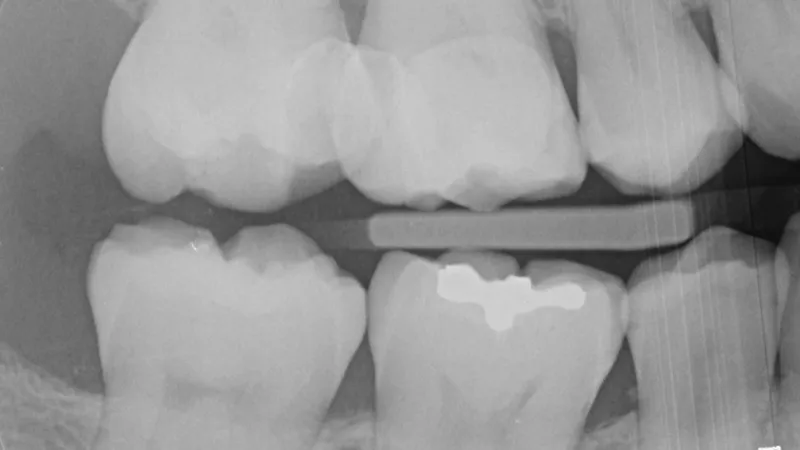

Restorative dentistry is undergoing a pivotal evolution, driven by the integration of 3D printed hybrid ceramic restorations into everyday clinical practice. In our experience, these restorations offer a clear step forward in both efficiency and precision. After completing thousands of prints, we’ve consistently found that 3D printed inlays, onlays, and crowns outperform traditional direct resin and CEREC-milled alternatives in workflow and clinical reliability. In this case study, we share our experience using this technology to improve clinical results.

The material used for 3D printed restorations is a methacrylate/acrylate polymer infiltrated with ceramic, offering mechanical and aesthetic properties similar to GC Cerasmart—a well-established milled composite. While compositionally alike, the key distinction lies in the production method: 3D printed restorations are additively manufactured, allowing for greater design flexibility and faster turnaround. When used for inlays and medium-sized onlays, these hybrid ceramics have demonstrated clinical longevity comparable to that of traditional ceramic crowns, as supported by studies on indirect composites and other hybrid materials.